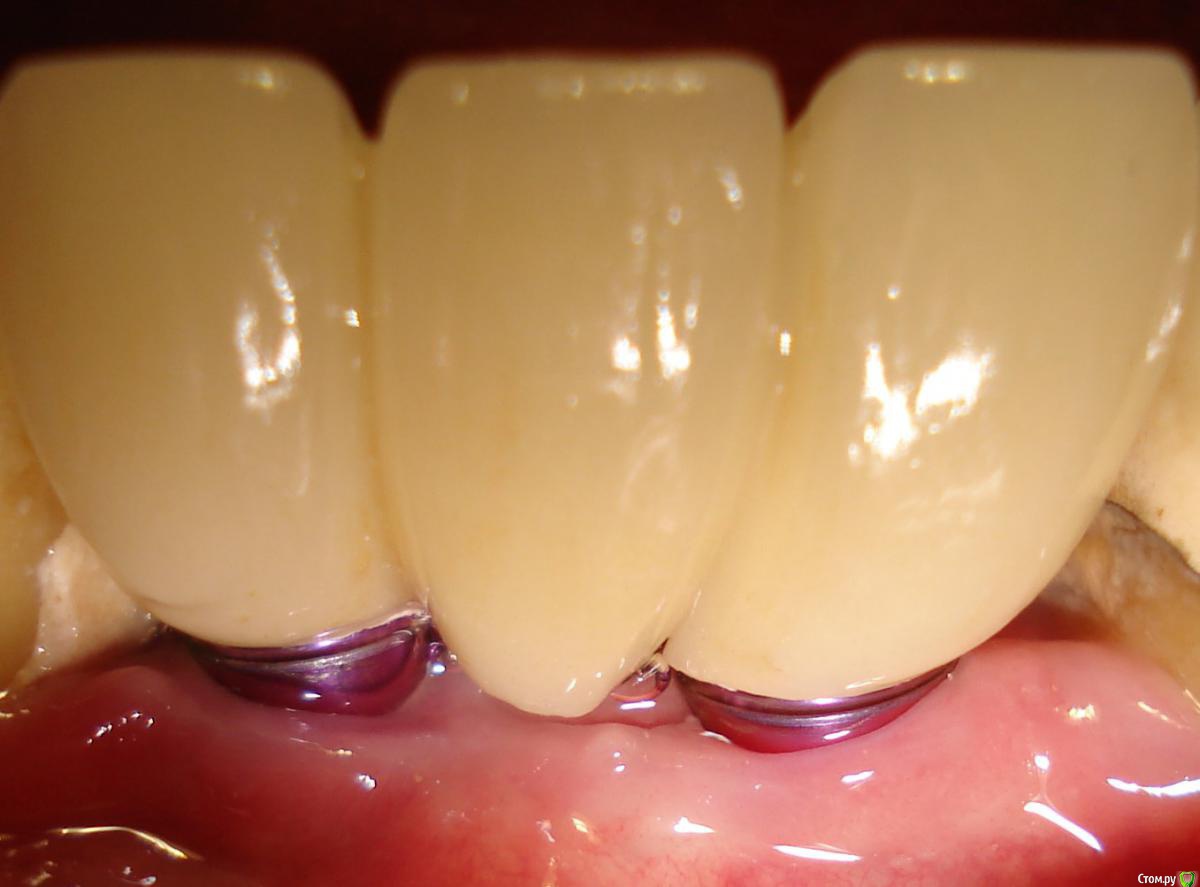

Antikwar Опубликовано 26 ноября, 2017 Поделиться Опубликовано 26 ноября, 2017 Доброго времени суток .Хотелось бы узнать компетентное мнение, врачей, З.техников. Вчера было установленно 2 моста (оксид циркония) на имплантанты перед низ и 2 коронки с боку правая сторона низ ..НА мой не опытный взгляд конструкция и сама работа не качественная и эстетика здесь полностью отсутствует. 1.Видно тело абатмента в обоих конструкциях. 2.Мост и коронки висят в воздухе и не прилегают к десне,как в первом так и во втором случае. Между десной и мостом (перед низ) проходит спичка. Вопрос, должен ли мой доктор переделать эту (на мой взгляд) не качественную работу ! Что вы мне посоветуете .... Заранее благодарю всех откликнувшихся. Ссылка на комментарий

chervoncevdaniil Опубликовано 26 ноября, 2017 Поделиться Опубликовано 26 ноября, 2017 Доброго времени суток .Хотелось бы узнать компетентное мнение, врачей, З.техников. Вчера было установленно 2 моста (оксид циркония) на имплантанты перед низ и 2 коронки с боку правая сторона низ ..НА мой не опытный взгляд конструкция и сама работа не качественная и эстетика здесь полностью отсутствует. 1.Видно тело абатмента в обоих конструкциях. 2.Мост и коронки висят в воздухе и не прилегают к десне,как в первом так и во втором случае. Между десной и мостом (перед низ) проходит спичка. Вопрос, должен ли мой доктор переделать эту (на мой взгляд) не качественную работу ! Что вы мне посоветуете .... Заранее благодарю всех откликнувшихся.СУдя по фото у вас убыль костной и мягких тканей в области ипмлантов.А состояние соседних коронок на зубах вас не смущают? Ссылка на комментарий

chervoncevdaniil Опубликовано 26 ноября, 2017 Поделиться Опубликовано 26 ноября, 2017 Конечно же смущает,.... но они в плане на лечение.НО как же ответ на мой вопрос ?Так это и есть ответ на ваш вопрос,конечно по фото судить сложно,нужен рентген,но если это убыль костной ткани,то коронки могут быть досажены корректно,относительно импланта,проблема может быть в том,что уже кость ушла ниже уровня имплантата,а это коронкой не перекрыть никак 2 Ссылка на комментарий

chervoncevdaniil Опубликовано 26 ноября, 2017 Поделиться Опубликовано 26 ноября, 2017 А, что нельзя сделать коронки по больше, что бы они легли на десну, ведь так просто????Если то,что выступает над десной уже сам имплант,а не абатмент(а скорее всего так оно и есть),то нельзя Ссылка на комментарий

krokomot Опубликовано 27 ноября, 2017 Поделиться Опубликовано 27 ноября, 2017 целевая зона на снимке замылена, четкости нет, исходя из ваших фотографий проблемма не в коронках, а в позиции имплантатов - видна шейка имплантата, так быть не должно. нужны прицельные снимки этой области. Учитывая обстоятельства коронки изготовливаются исходя из положения имплантатов.и я так понимаю вас запротезировали из позиции то что есть, и вая явно нужно что-то делать. Ссылка на комментарий